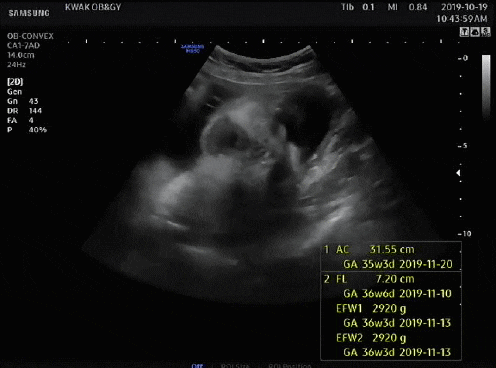

지금은 36주부터 출산까지 매주 목요일 병원에 가서 NST를 통해 태아의 움직임과 심박수, 자궁수축을 기록해 태아가 잘 있는지 확인하고 있다.

엄마가 음식(특히 단것)을 먹으면 움직임을 측정하기 쉽다고 한다. 기계 도면으로 인해 태아는 아침보다 밤에 더 활동적이어서 검사 중에는 움직임을 많이 잡지 못했으나 여전히 정상 범위 내이며 심박수는 130~130 사이에서 관찰하기 쉽습니다. 170. 1차 검사에서 큰 1개, 작은 3~4개 적발돼 정상이었다. 분만 시 자궁수축이 더 잦아진다고 하는데, 분만 브이로그를 보면 분만 당일 강도가 100을 넘는 게 규칙적이다. B-초음파는 양수의 양과 태아의 위치를 확인하기 위해 매주 할 수 있는 것 같고, 양막의 크기는 큰 것 하나, 정상인 것 하나 총 두 번 측정했다. 응! ! ! ! ! ! ! ! ! 긴 의료 설명, 의사가 마지막에 추가했습니다. 정상, 괜찮습니다. 동양인 엄마의 체형(골반), 아기의 머리둘레, 회음부절개에 대해 물어봤습니다. 미국에서는 관장, 제모, 외음절개술을 시행하지 않는 것으로 알려져 있지만 외음절개술이라면 의학적으로 필요하거나 필요하다고 합니다. 머리둘레 걱정했는데 제왕절개까지 고려하기엔 역부족이었고(조건은 자연분만일 수 없음: 아기의 몸무게는 5kg임), 산도에서 나오면 아기의 머리 모양이 질 입구에 딱 맞으니 걱정하지 마세요. 걱정되는 저를 안심시키기 위해 의사선생님께서 의료진이 최선을 다해 도와드리겠다고 말씀해주셨습니다. 저도 오늘 B초음파를 하는 이유가 궁금했는데 그게 아니라서 모른다고 하더군요. 이유. 미국의 대답. 오늘 만난 의사는 최근 이상한 변호사 Wu Yingyu를 보는 것을 즐겼다고 말했습니다. 그래서 치료받는 내내 웃음을 참을 수 없었습니다. 덕분에 불안한 마음이 많이 진정되었어요~ 산모가방 싸기 파워J형 K형 산모가방 미국 병원에 있어요~ 정상분만 1박2일만에 퇴원하고 3일만에 그리고 제왕절개 2박.. 한국처럼 큰소리로 산부인과 가방을 싸갈 필요도 없고, 준비물은 다 구비되어 있다고 해서 퇴원할 때 아기옷, 잠옷, 기타 등등 챙겨가셔야 합니다. 산모에게 안정적인 담요를 제공할 수 있는 것. 필요없으시면 다시 가져가시면 됩니다. 필요하지만 그것 없이는 살 수 없습니다. 그래서 제가 챙겨가는 것은 여권, 보험증, 속옷(수유브라), 수면양말, 겉옷, 면속옷, 수유패드, 수유패드, 가슴확대키트, 유축기, 유두보호대, 손목싸개, 회음부패드, 비데, 영양제, 임부복(산모안전속옷), 생리대(1박), 세면도구, 구강청결제, 립밤, 헤어밴드, 기초화장품, 스트레치마크크림, 실내슬리퍼, 휴대폰충전기, 보조배터리, 마스크, 알약, 간식 /다과, 카시트, 포대기, 핸드백, 포장지(담요), 거즈손수건, 젖병, 겉옷(바디슈트), 아기모자, 물티슈, 비타민D, 유산균* 출생신고가 필요하여 퇴원 전 아기의 이름을 정했습니다. 아기의 이름은 최종 후보 2명까지 고려 중이지만, 생년월일과 시간을 보고 최종 결정하게 된다. 산부인과/산부인과/학과 전문용어 외우기 언어차이 극복 미국에서 출산이라는 번거로운 일을 앞두고 가장 걱정되는 것이 언어와 문화차이인 것 같아요. 언어차이는 있지만 통역사들이 있긴 한데… 통역사들의 질이 별로 좋지 않고, 케이블에 제약이 있어서 아기가 생기면 통역사를 안 쓸 생각입니다. 생명이 위급한 상황에서 자신을 보호하기 위해 관련 용어를 숙지합니다. 조산전 산부인과 산부인과 GYN 산부인과 소아과 소아과 둔위전위 태반 미숙아/미숙아 양수 양막 양막 양막 SROM(자발성 막 파열) 파열, 양막 파열 태반 태반 임신 전 당뇨 거림메스꺼움 데데이트, EDD(예상분만일), 자연분만, 자연분만, 제왕절개, 제왕절개, 태아태아, 지진마사지, 막스윕입원, 병원 둘라 / 자간전증이 있는 임산부(증상: 단백뇨, 두통, 부종 등) 저혈압, 저혈압(체외수정) 비스트레스 검사(NST) 경험, 임산부가 편안하게 눕힌 후 20분 동안 산모의 복벽에 모니터를 설치하여 태아 심박수 모니터링 파악 태아의 건강 상태 분만(시간), 분만(과정) 분만, 분만 분만 수축 분만 수축 실제 분만 수축은 점액 마개를 드러내고, 혈액은 자궁 수축을 보여줍니다. 미국 선택, 필요한 경우 37-8주부터 시작) 자궁경부 검사, 내부 검사 내가 확장되고 있는지 확인할 수 있습니까? 확장(자궁문이 열림을 나타냄/0-10cm) 무통 경막외 마취 주사 태아 운동 분만 유도, 분만 유도 흑선 외음절개 회음부(또는 질) 열상(또는 열상) 1도 열상: 1도- 2도 열상(피부 및 피하 조직에 한하며 심한 출혈을 일으킬 수 있는 요도주위 열상 포함) – 2도 열상: 2도 열상(질 괄약근의 근막 및 근육층에 나타나며 항문 괄약근은 영향을 받지 않음) – 3도 열상 열상: 3도 열상(항문 괄약근 및 직장질 횡격막에 영향을 미침) -4도 열상: 4도 열상 상부(항문 및 직장 점막에 영양 공급, 이때 완전히 치료하지 않으면 직장질 누공으로 이어질 수 있음) 관장 산도 탯줄, 탯줄 겸자 산파, 겸자 조산 진공 펌핑 회전(알코올) 버전 정맥주사, 정맥주사 담당의사가 담당의사 대기 중 의사가 퇴원하여 신생아 집중치료실 NICU가 저림 및 출혈 산후출혈 산후 통증 초유, 분유 전 황색 산후 2~3일 묽은 분비물 모유 수유 중 태변 황달/황달 모유 수유 금이 간 유두 황달, 수유 중 또는 수유 사이에 지속적인 유두 통증, 유방 충혈, 분만 후 유방 통증 또는 전신 모유 수유 염증, 유방 통증 유륜 건선 Fluff Lanugo Sitz B형 간염 연고 가임력 산모 피임약 GBS Bacterial Check (37주 + 5회) Group B Streptococcus Bacterial Check 임산부의 질이나 직장에 상주하는 GBS(Streptococcus B)는 신생아 패혈증 및 수막염의 주요 원인 . 신생아가 GBS에 감염되면 일부는 사망하고 생존하더라도 합병증이 발생해 후유증을 동반할 수 있다. GBS는 임산부의 생식기나 위장관에 특별한 증상이 없지만 자궁이나 출산 중 감염을 일으킬 수 있습니다. 따라서 35~37일 말에 GBS 검사에서 양성 반응을 얻으면 분만 내내 항생제나 조치를 취해야 한다. 흔한 세균이고 산모 4-5명 중 1명이 양성 반응을 보여서 크게 걱정하지는 않지만 음성 반응이 나오기를 바라고 있습니다. 개별 포장된 의료용 면봉으로 질입구 -> 직장입구 순으로 5~7회 이상 닦은 후 면봉봉을 절취선에 따라 부러뜨린 후 용기에 삽입합니다. 1~2분 정도 소요되며 매우 간단합니다. 코로나 자가진단키트 느낌. 결과는 며칠 이내에 앱을 통해 받을 수 있습니다. 지난달 메디신볼 운동으로 골반이 활짝 열렸으니 계속 해보세요! 도움을 받을 수 없는 상황이기 때문입니다. 그래서 37주차에 들어가면서 하루에 30분씩 런닝머신 + 엑서사이즈 볼을 하고 있습니다. 내 골반이 부드러워졌으면 좋겠다. . . 집에서 운동을 많이 하지는 않는데 이 영상은 15분짜리입니다. 시간가는 줄 모르고 그냥 따라갔어요. 남편과 소중한 시간을 보내세요. 한동안 우리 집에서 조용한 시간은 없을 텐데(feat. 칼리 날씨) 이제 부모님 오실 날도 일주일 앞으로 다가왔습니다. 그들은 친밀한 시간을 보내고 있습니다. 육아에 직격탄을 맞으면 임시 연애는 어려울 수 있다. 결혼 후 3년간의 격렬한 놀이, 술, 여행. 그들은 신혼부부로서 할 수 있는 모든 일에 자부심을 가지고 있습니다. 슬프다, 이상하다고 생각한다. 캘리포니아의 날씨는 요즘 늦봄(15~20도) 같아서 공원에 가서 샌드위치+커피를 먹기도 좋고, 교외를 드라이브하며 맛집을 찾아 다니기도 좋고… 마지막인 것 같아서 더 재밌어요 ㅎㅎ 밖에 나가야 할 정도로 먼 길을 갈 수는 없었지만, 가까이 있다는 소소한 행복이 출산의 설렘을 달랬습니다. 부모님이 오신 후에도 우리 가족은 적어도 일주일 동안 외식을 하고 당일치기 여행을 할 수 있었습니다. 원하다… !